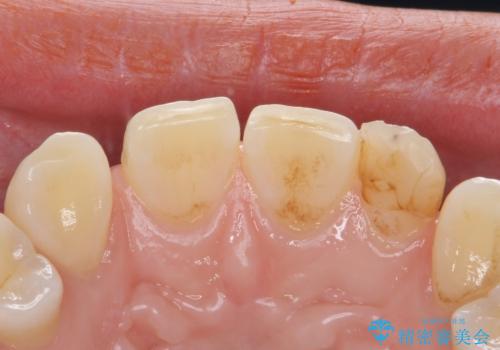

変色した前歯をキレイにしたい ジルコニアクラウンでの修復

- 左上の前歯の変色が気になるとのことで来院されました。

もともと小さい歯(矮小歯)に樹脂が盛り足されている状態でした。

今後の変色をなくすために樹脂ではなくセラミックでの治療を行います。